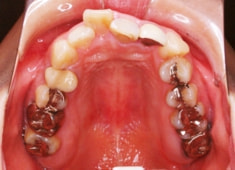

治療開始から1年8ヶ月後